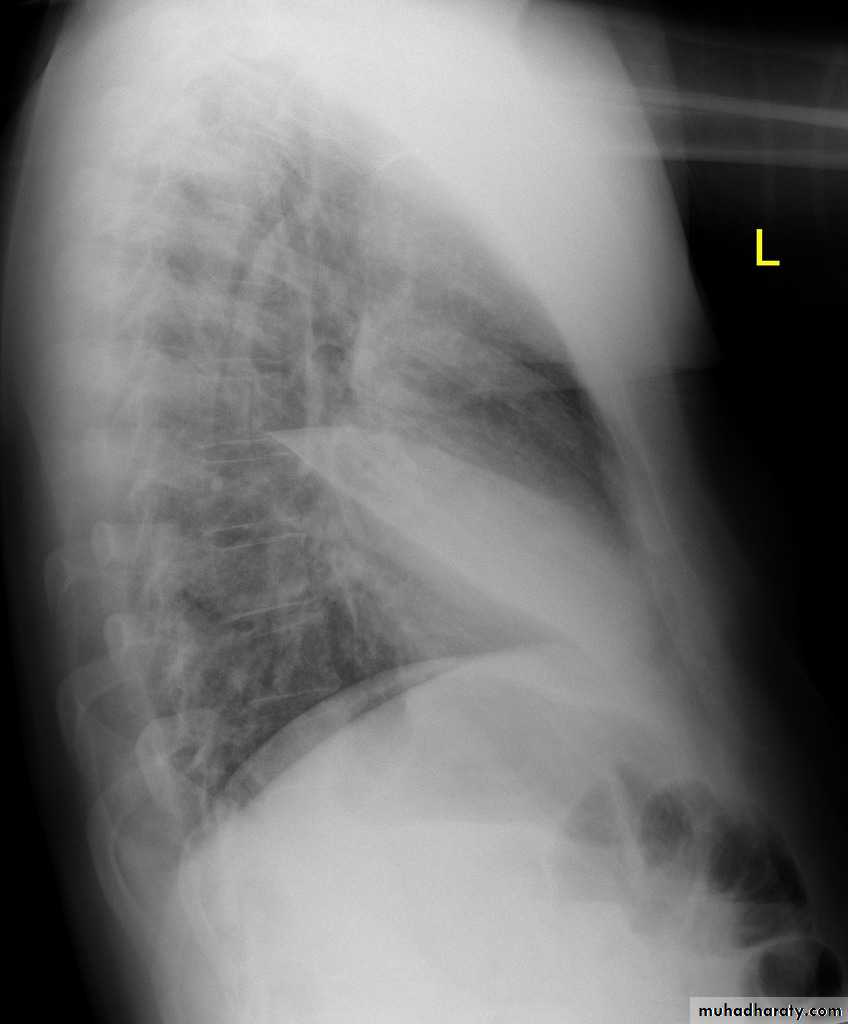

Left lower lobe collapse has distinctive features, and can be readily identified on frontal chest radiographs, provided attention is paid to the normal cardiomediastinal contours. The shadow cast by the heart does however make it harder to see than the right lower lobe collapse

Radiographic features

Left lower lobe collapseis readily identified in a well penetrated film of a patient with normal sized heart, but can be challenging in the typical patient with collapse, namely unwell patients, with portable (AP) often under-penetrated films, often with concomitant cardiomegaly. Features to be observed include :

triangular opacity in the posteromedial aspect of the left lung

edge of collapsed lung may create a 'double cardiac contour'

left hilum will be depressed

loss of the normal left hemidaphgragmatic outline

loss of the outline of the descending aorta

Non-specific signs indicating left sided atelectasis are usually also be present including:

elevation of the hemidiaphragm

crowding of the left sided ribs

shift of the mediastinum to the left

On lateral projection the left hemidiaphragmatic outline is lost posteriorly and the lower thoracic vertebrae appear denser than normal (they are usually more radiolucent than the upper vertebrae) .